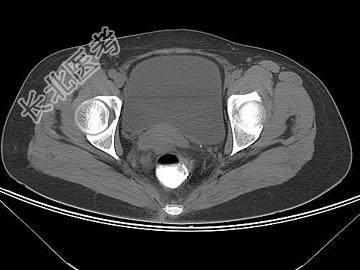

- 单项选择题女,67岁, 排便习惯改变,血便3月入院, CT检查如图所示,下列说法错误的是 ( )

A、直肠肠腔局限性增厚

B、其表面欠光整,边界欠清晰

C、可做直肠指检及活检以确定病变性质

D、此为直肠息肉

E、此为直肠癌